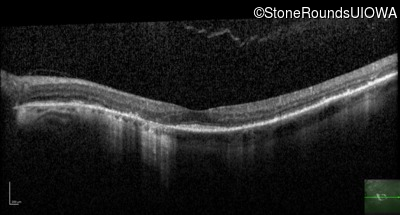

Age at visit: 62 years

This 62 year old man first noted mild distortion in his vision in his 30's, but has always been correctable to 20/20. One year ago an optometrist told him there were pigment abnormalities in his macula.

Diagnosis & molecular findings

Disease Gene Allele 1 variant(s) Allele 2 variant(s) Inheritance mode

Pattern Dystrophy PRPH2 Lys153Glu AAG>GAG   AD